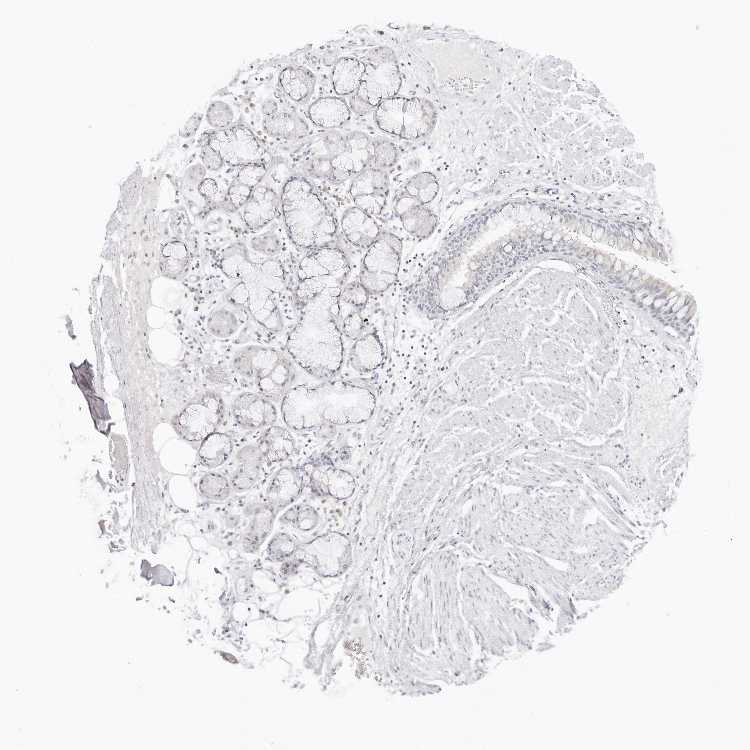

SOFT TISSUE 1 - Antibody stainingi

Antibody staining in the annotated cell types in the current human tissue is reported as not detected, low, medium, or high, based on conventional immunohistochemistry profiling in selected tissues. This score is based on the combination of the staining intensity and fraction of stained cells.

Each image is clickable and will lead to virtual microscopy that enables deeper exploration of all samples and also displays staining intensity scores, fraction scores and subcellular localization as well as patient and tissue information for each sample.

Antibody HPA028459

Fibroblasts Not detected

Peripheral nerve Not detected